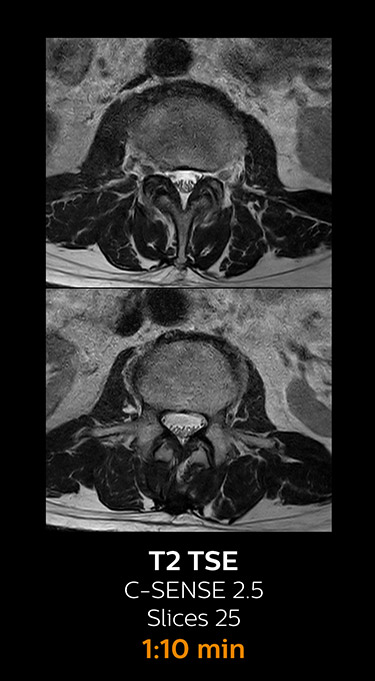

which corresponds to 34% reduction.

With Compressed SENSE, the scan time for the routine lumbar spine examination at KNC was reduced from 11:41 to 8:17 minutes,

MRI examination of the lumbar spine with Compressed SENSE

Ingenia 3.0T CX

Scan time 8:17 min. (was 11:41 min. without Compressed SENSE)